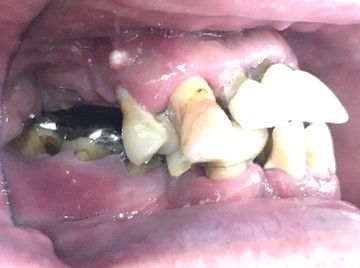

女性Tさん 50代(マグネット式入れ歯)

主訴

左上の犬歯が、グラグラして痛い

治療内容

他の歯も歯周病が進行していました。保存することができない歯が3本ありましたので、抜歯し、残った歯6本の歯周病治療をし、それらの歯を活用しマグネット式総入れ歯を入れました。

所感

マグネット式総入れ歯を活用し、もともとは反対交合でしたが、正常交合に改善することができました。

Before

赤丸は抜歯しました

After

【義歯を装着したところ】